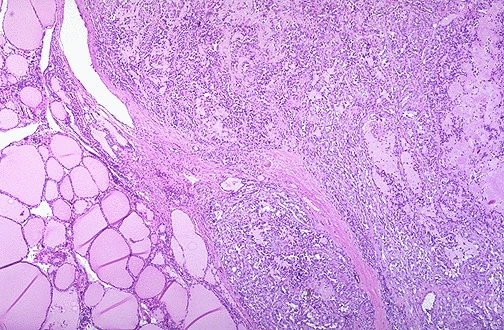

| At the center and to the right is a medullary carcinoma of thyroid. At the far right is pink hyaline material with the appearance of amyloid. These neoplasms are derived from the thyroid "C" cells and, therefore, can have neuroendocrine features such as secretion of calcitonin or other hormones. |